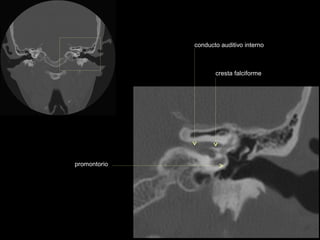

cresta falciforme

promontorio